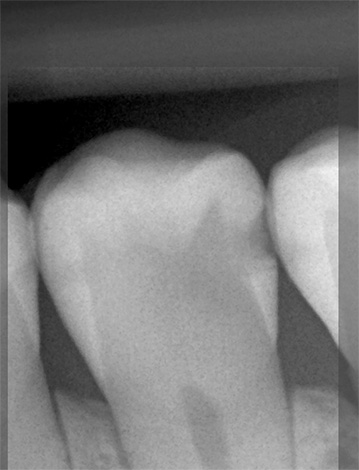

Un esempio di carie profonde in una radiografia è mostrato di seguito:

! importante

La carie profonda può svilupparsi anche senza lesioni visibili sulla superficie del dente. Sulla radiografia è chiaramente visibile e quindi spesso viene scattata una foto per diagnosticare e determinare l'estensione della lesione.